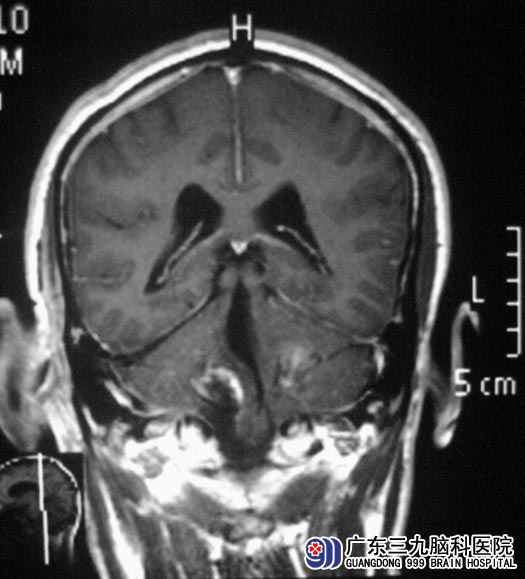

在广东三九脑科医院综合神经外科住院后,进一步MR检查发现:“双侧桥小脑角区多发占位性病变,左侧听神经增粗、强化,大小约30.6mm×29.1mm×33.7mm;右侧听神经未见强化,大小约为32.7mm×26.9mm×47.6mm,肿瘤向下生长入颈静脉孔”;考虑多发神经鞘膜瘤。